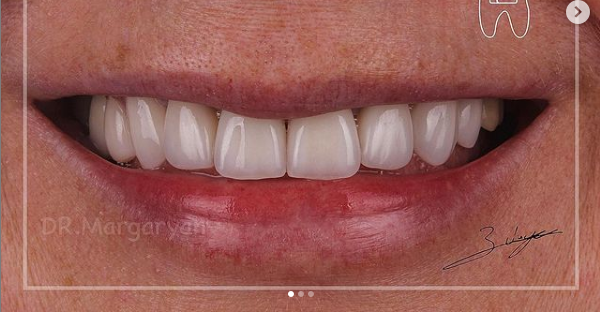

12 работ в портфолио

Маргарян Эдуард Вадимович принимает в МЕДИЦИНСКОМ СТОМАТОЛОГИЧЕСКОМ ЦЕНТРЕ НА ЗЕЛЕНОГРАДСКОЙ в Москве. Стаж 13 лет. Специализируется на ортопедии. Имеет 12 работ до/после в портфолио. Для уточнения дополнительной информации о специалисте или записи на прием можно позвонить по телефону

Установка керамических виниров

Установка виниров E-max